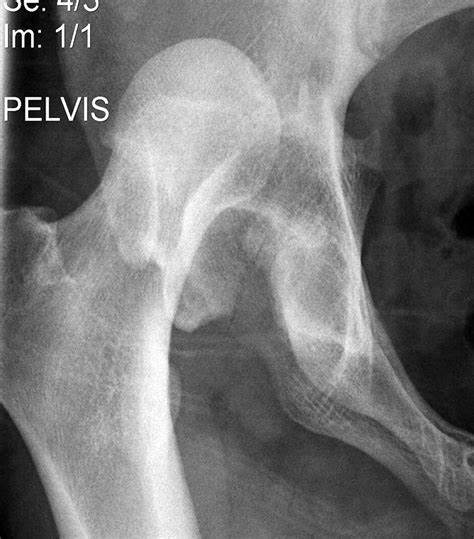

الصورة الشعاعية الأمامية للحوض (AP pelvis) أكدت وجود خلع خلفي لمفصل الورك الأيمن.

الخلع الخلفي لمفصل الورك (Posterior Hip Dislocation)

وهو النوع الأكثر شيوعًا (>90%) من خلع الورك في الإصابات الرضية.